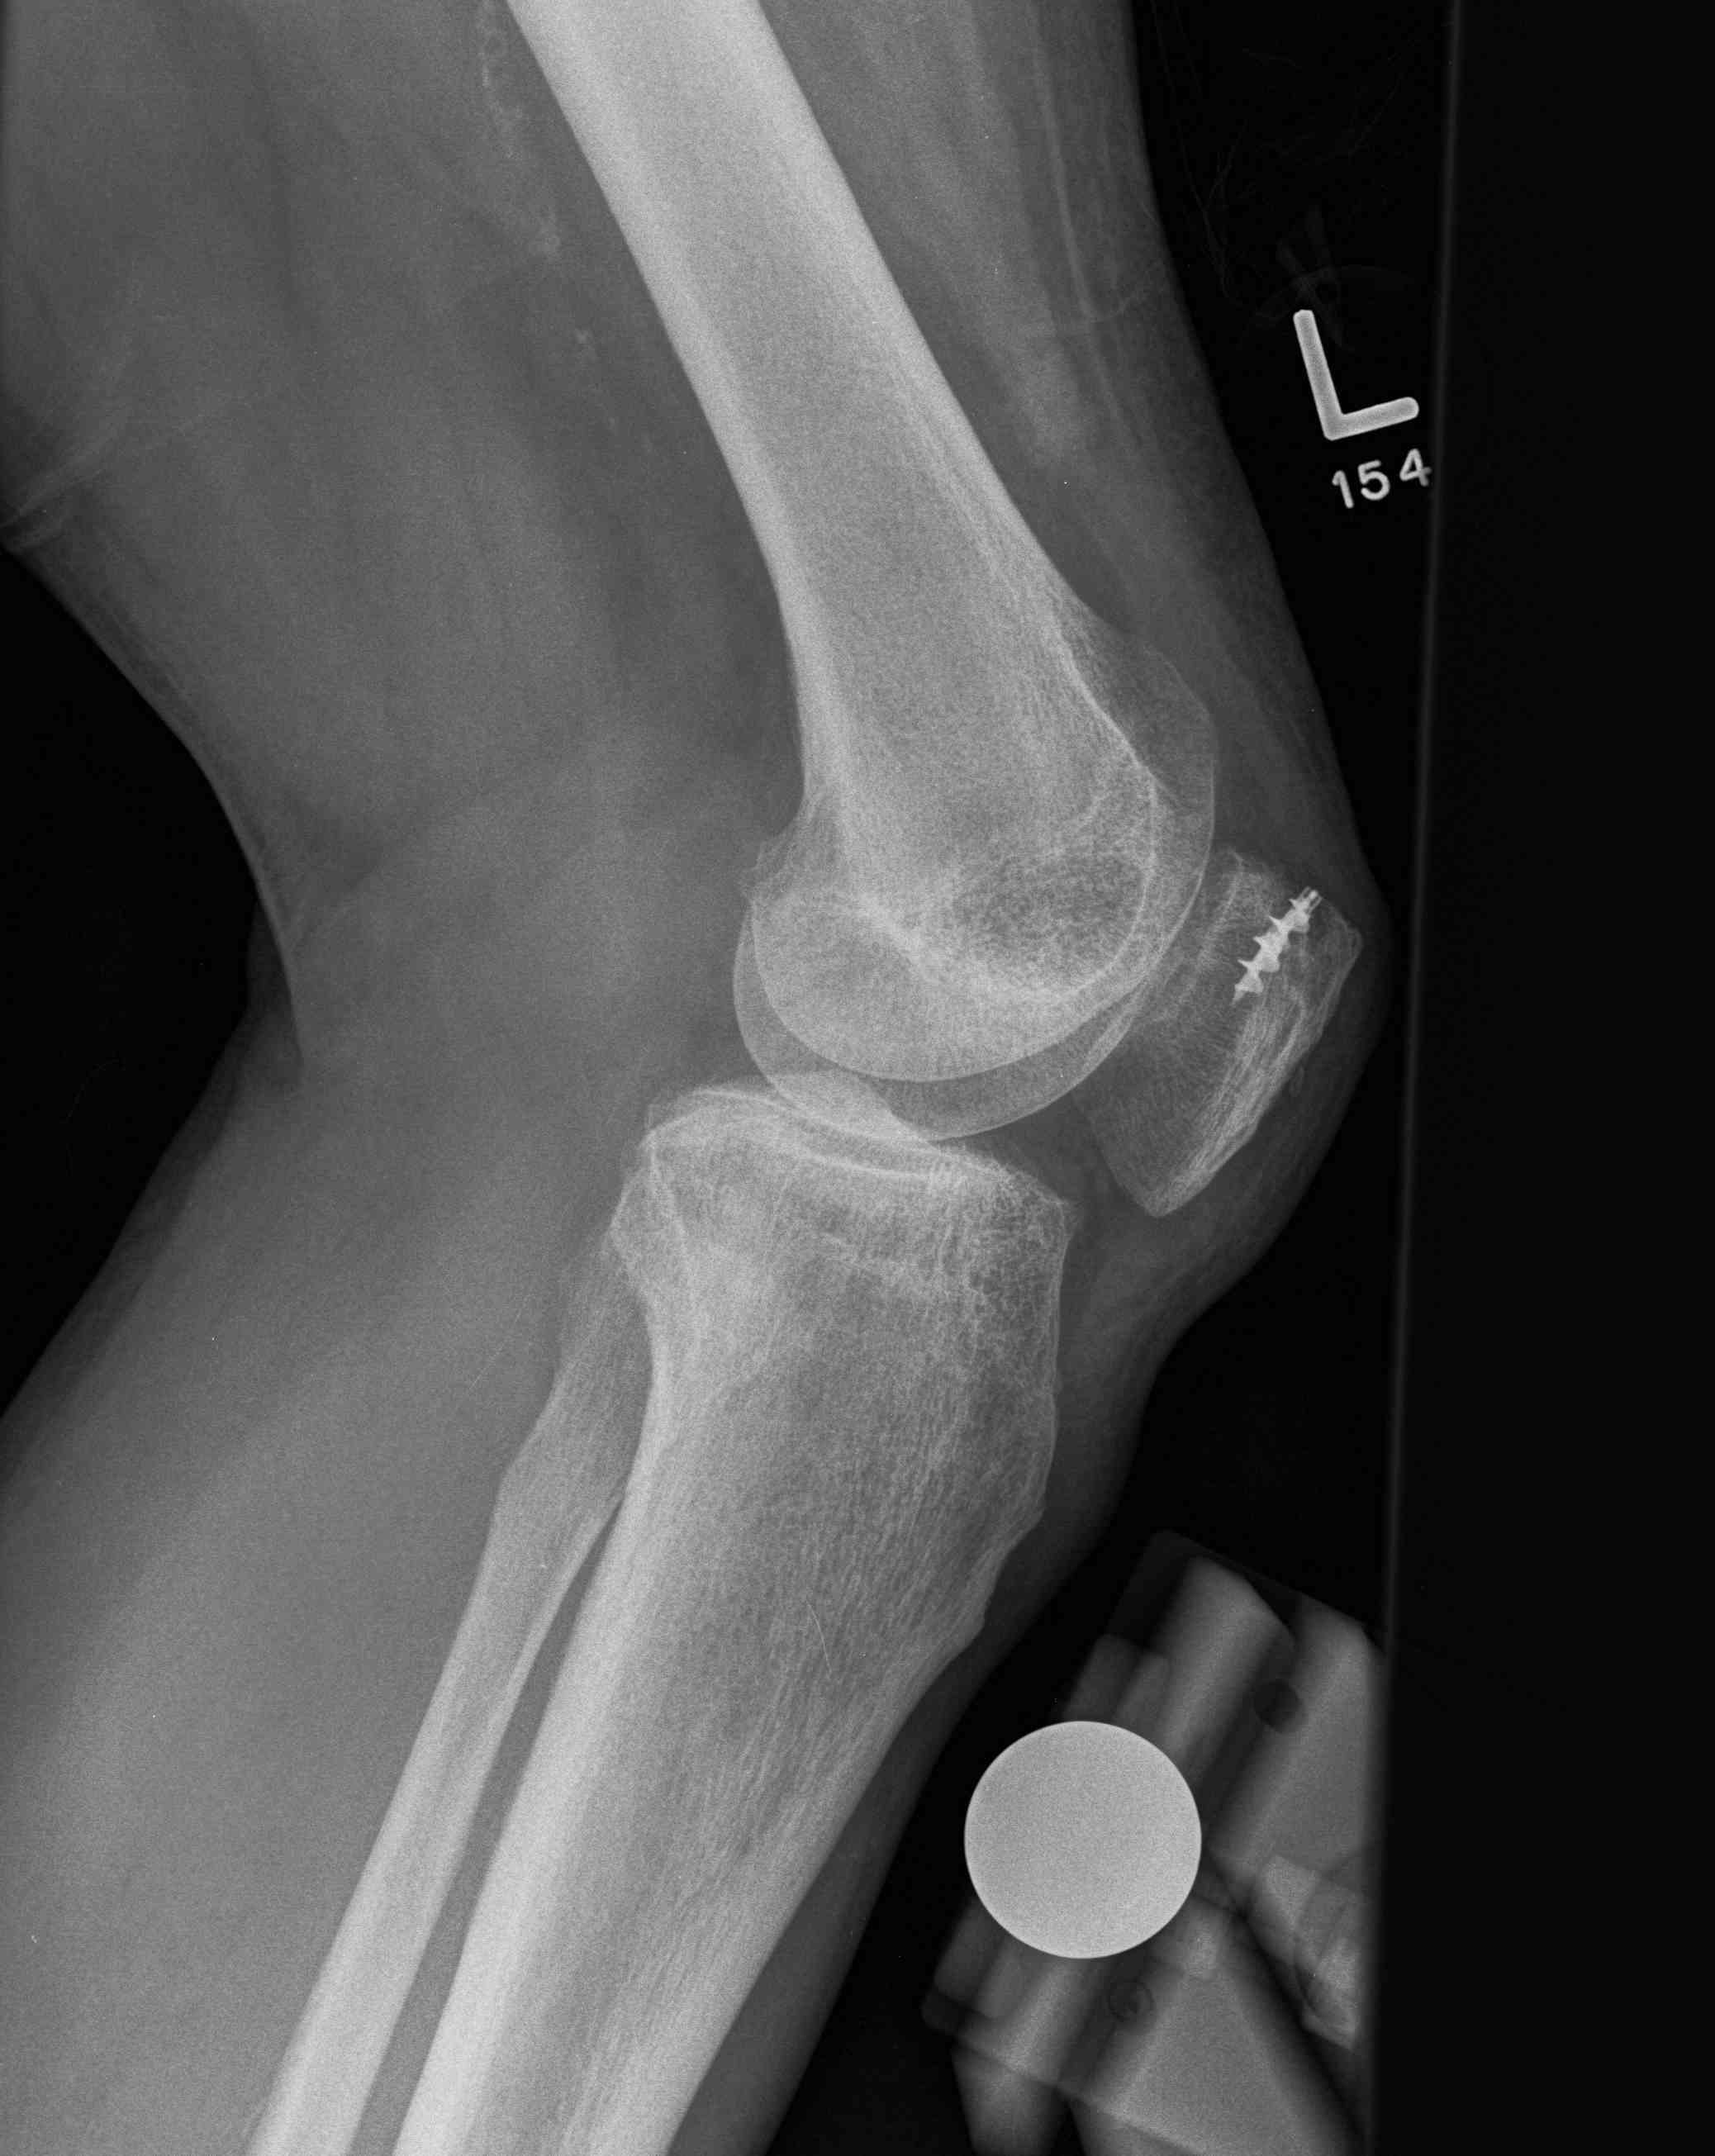

Xray

Patella Baja